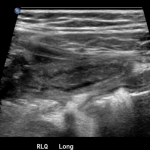

In the long axis video, the appendix appears as an enlarged, non-compressible, blind-ending tubular structure (white arrow) with distinct appendiceal wall layers and lack of peristalsis. In the short axis video, the appendix appears as a target sign (yellow arrow) between the abdominal and psoas muscles. The maximal outer diameter (MOD) measures 11.8mm and the appendix wall measures 0.17mm. There is trace adjacent free fluid and echogenic periappendiceal fat. Transverse axis video and image (red arrow) demonstrate that the appendix is not compressible. These findings are consistent with acute appendicitis.

Acute appendicitis is the most common surgical emergency in the pediatric population, with an annual incidence of 119.7 cases/100,000 in children of age 0-19 years.1,2 Given children’s limited ability to communicate their symptoms and the radiation risks associated with computed tomography, ultrasound is a particularly valuable tool for diagnosing appendicitis in children. It has a sensitivity and specificity of 88% and 94%, respectively, compared to the 94% sensitivity and 95% specificity seen for CT studies.3,4 Frequent use of ultrasound and clear visualization of the appendix during exam improve sensitivity.2 Currently, the diagnostic criteria for appendicitis includes a MOD of compressed appendix >6mm (most specific sign) and an appendix wall thickness ≥3 mm.4,5 A retrospective review at one institution found that the highest sensitivity (98.7%) and specificity (95.4%) were achieved when MOD was ≥7 mm or wall thickness was >1.7 mm.5 Male gender, increased age, and body mass index percentiles ≥85 are associated with non-diagnostic ultrasound.6,7 Use of lower frequency curvilinear transducer for retrocecal appendices and obese children and techniques such as posterior manual compression, where the operator’s left hand provides anterior force to the patient’s right lower back above the ileum to reduce the distance to the transducer, may be helpful.4